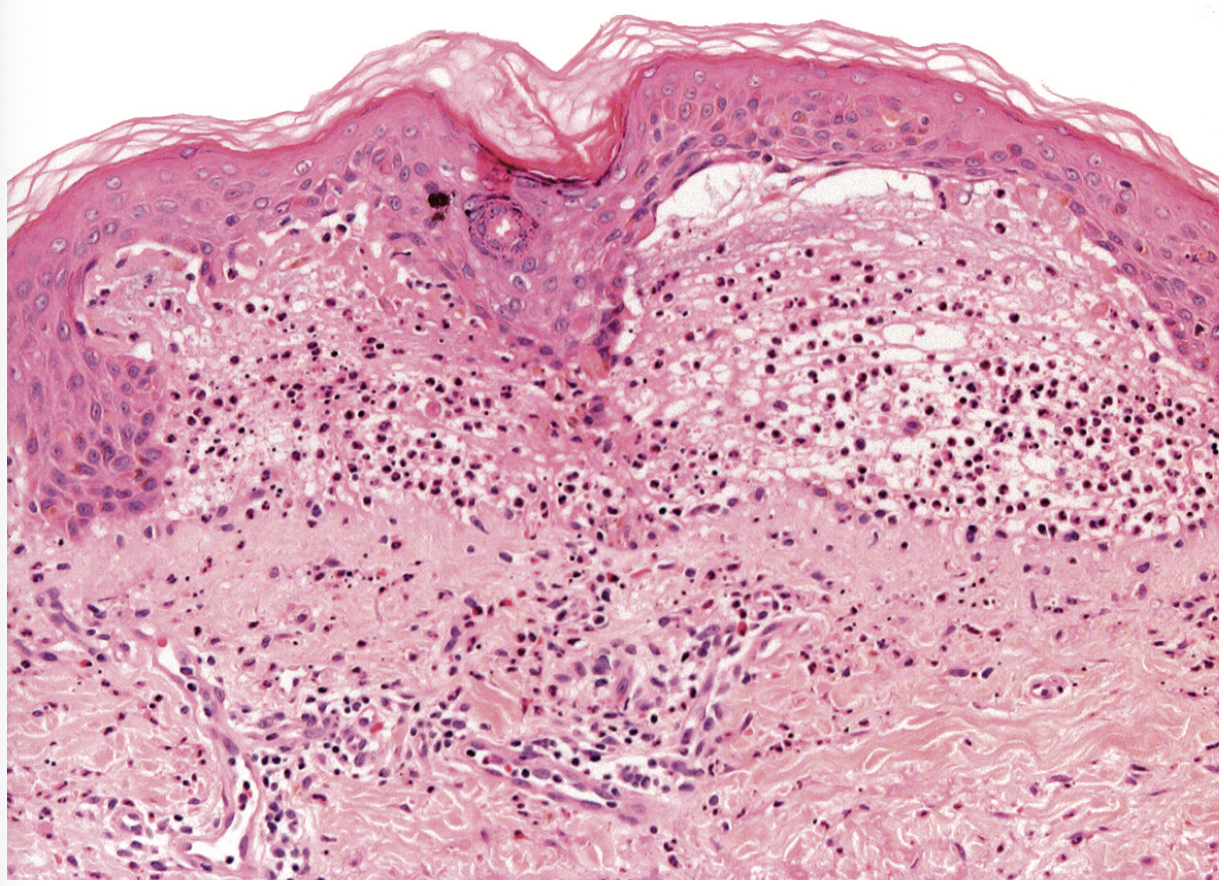

Histologie DIgAL

Dermatose vésiculeuse sous-épidermique à prédominance neutrophilique

Précoce

Neutrophiles alignés le long de la membrane basale

Changements vacuolaires

Parfois microabcès neutrophiliques dans les papilles dermiques

similaire à DH

Mature

Bulles sous-pidermiques

Neutrophiles derme sous-jacent

avec ou sans éosinophiles